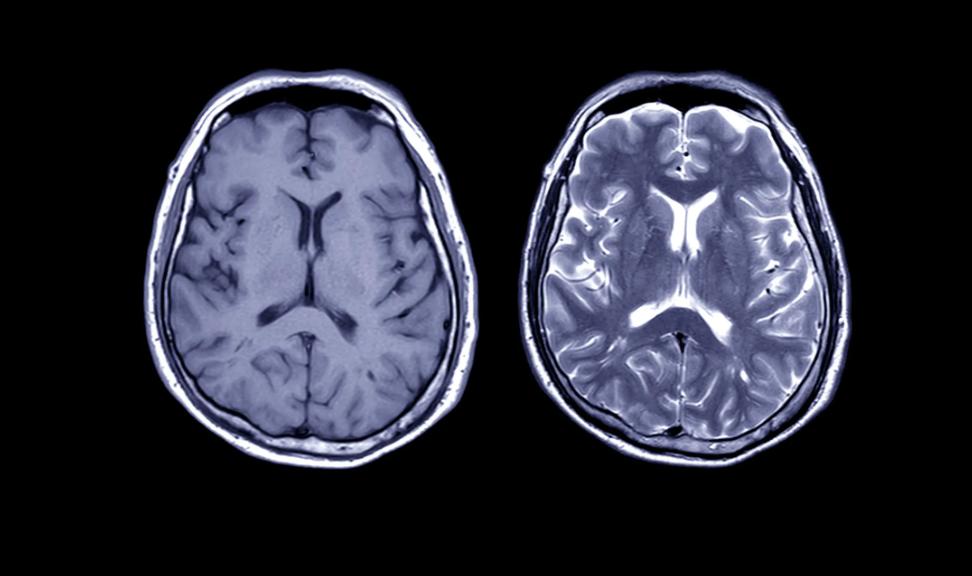

一天早上,她约了放射科医生会商几天前做的磁共振扫描结果。那天,她母亲也正在场。结果,索菲不停天插话,一句接着一句。"小脑有甚么病变的病症吗?"索菲问,"功用性磁共振成像做过了吗?丘脑、穹隆、脑桥的情况怎样?有无遭到影响?"

医生眉头皱了起去,锋利的目光瞥了一眼简,然后转回到索菲身上。"您是怎样明白那些的,索菲?"他问讲。索菲回答道,头几天她压服女亲从藏书楼里借了几本神经科教圆里的书。女亲把那些神经科教战年夜脑解剖规划圆里的讲义拿去后,索菲"不断读到了深夜"。